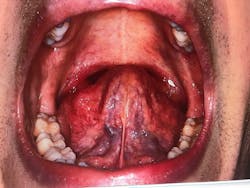

Figures 2 and 3: Crowding of the lower anterior teeth and scalloping of the tongue. These are common findings with airway and breathing disorders.

Figure 6: Extremely enlarged tonsillar tissue obstructing the posterior airway

Figure 7: Ankyloglossia—75% tongue-tie constriction